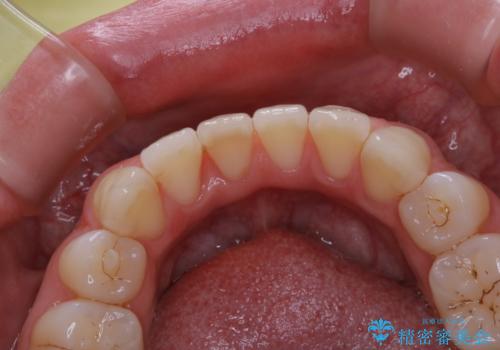

1年ぶりにPMTCで歯の着色落とし

- しばらく歯科医院へ行けなかったため、しっかり着色や汚れを落として欲しいとのことで来院されました。全体的に着色や歯石が付着していたためPMTC60分コースを行いました。